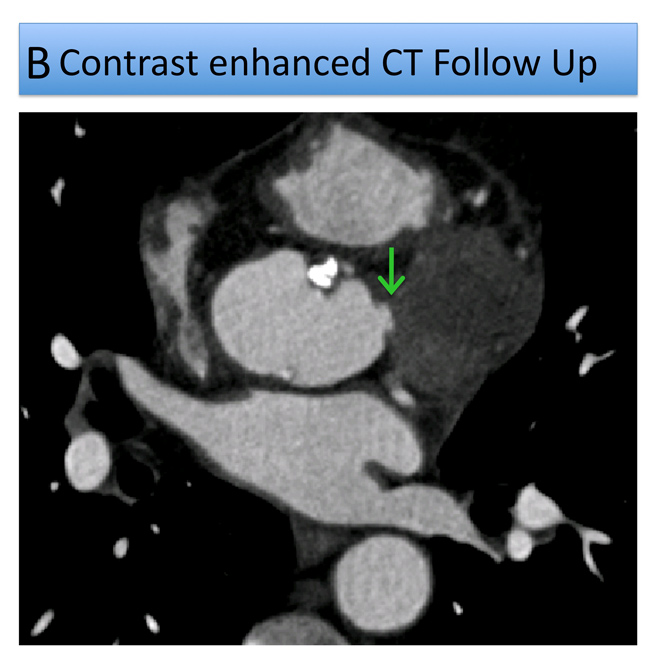

First pass perfusion demonstrated its communication with the aortic root but no extravasation of contrast into the pericardial space. There was also a small anterior transmural scar (Figure C, Video 1). During cardiac surgery a small, closed, dimple deep in a recess immediately above the annulus was visualized not needing further intervention (Figure B Follow Up CT arrow). On Follow Up CMR the structure did not show first pass perfusion and appeared to be thrombosed (Figure D, Figure E, Video 2). Diagnosis of a ruptured small aneurysm of the Sinus of Valsalva with extraaortic haematoma probably compromising a small branch coronary artery was made.